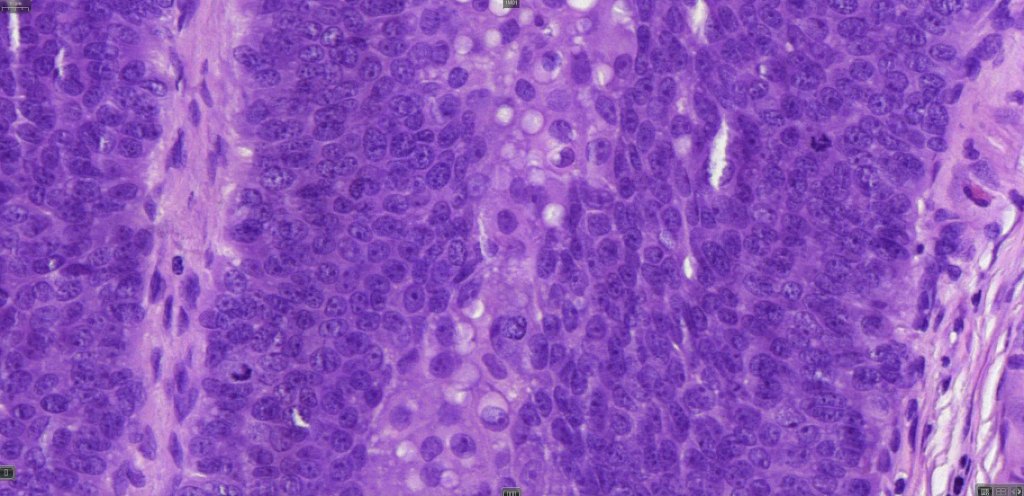

•Well differentiated examples can be deceptive unless one looks carefully for pleomorphism, necrosis, excessive mitotic activity and abnormal mitoses. Be careful diagnosing sebaceous adenoma, particularly large examples arising in the elderly

•Tumors are composed of an admixture of darkly staining basaloid cells with hyperchromatic or vesicular nuclei and more obvious sebaceous cells with eosinophilic, bubbly, multivacuolated cytoplasm frequently indenting the nucleus (scalloped)

•Often mitoses are numerous and abnormal forms evident

Sebaceous carcinoma from a patient with Muir-Torre syndrome kindly shared by Dr. Antonina Kalmykova.